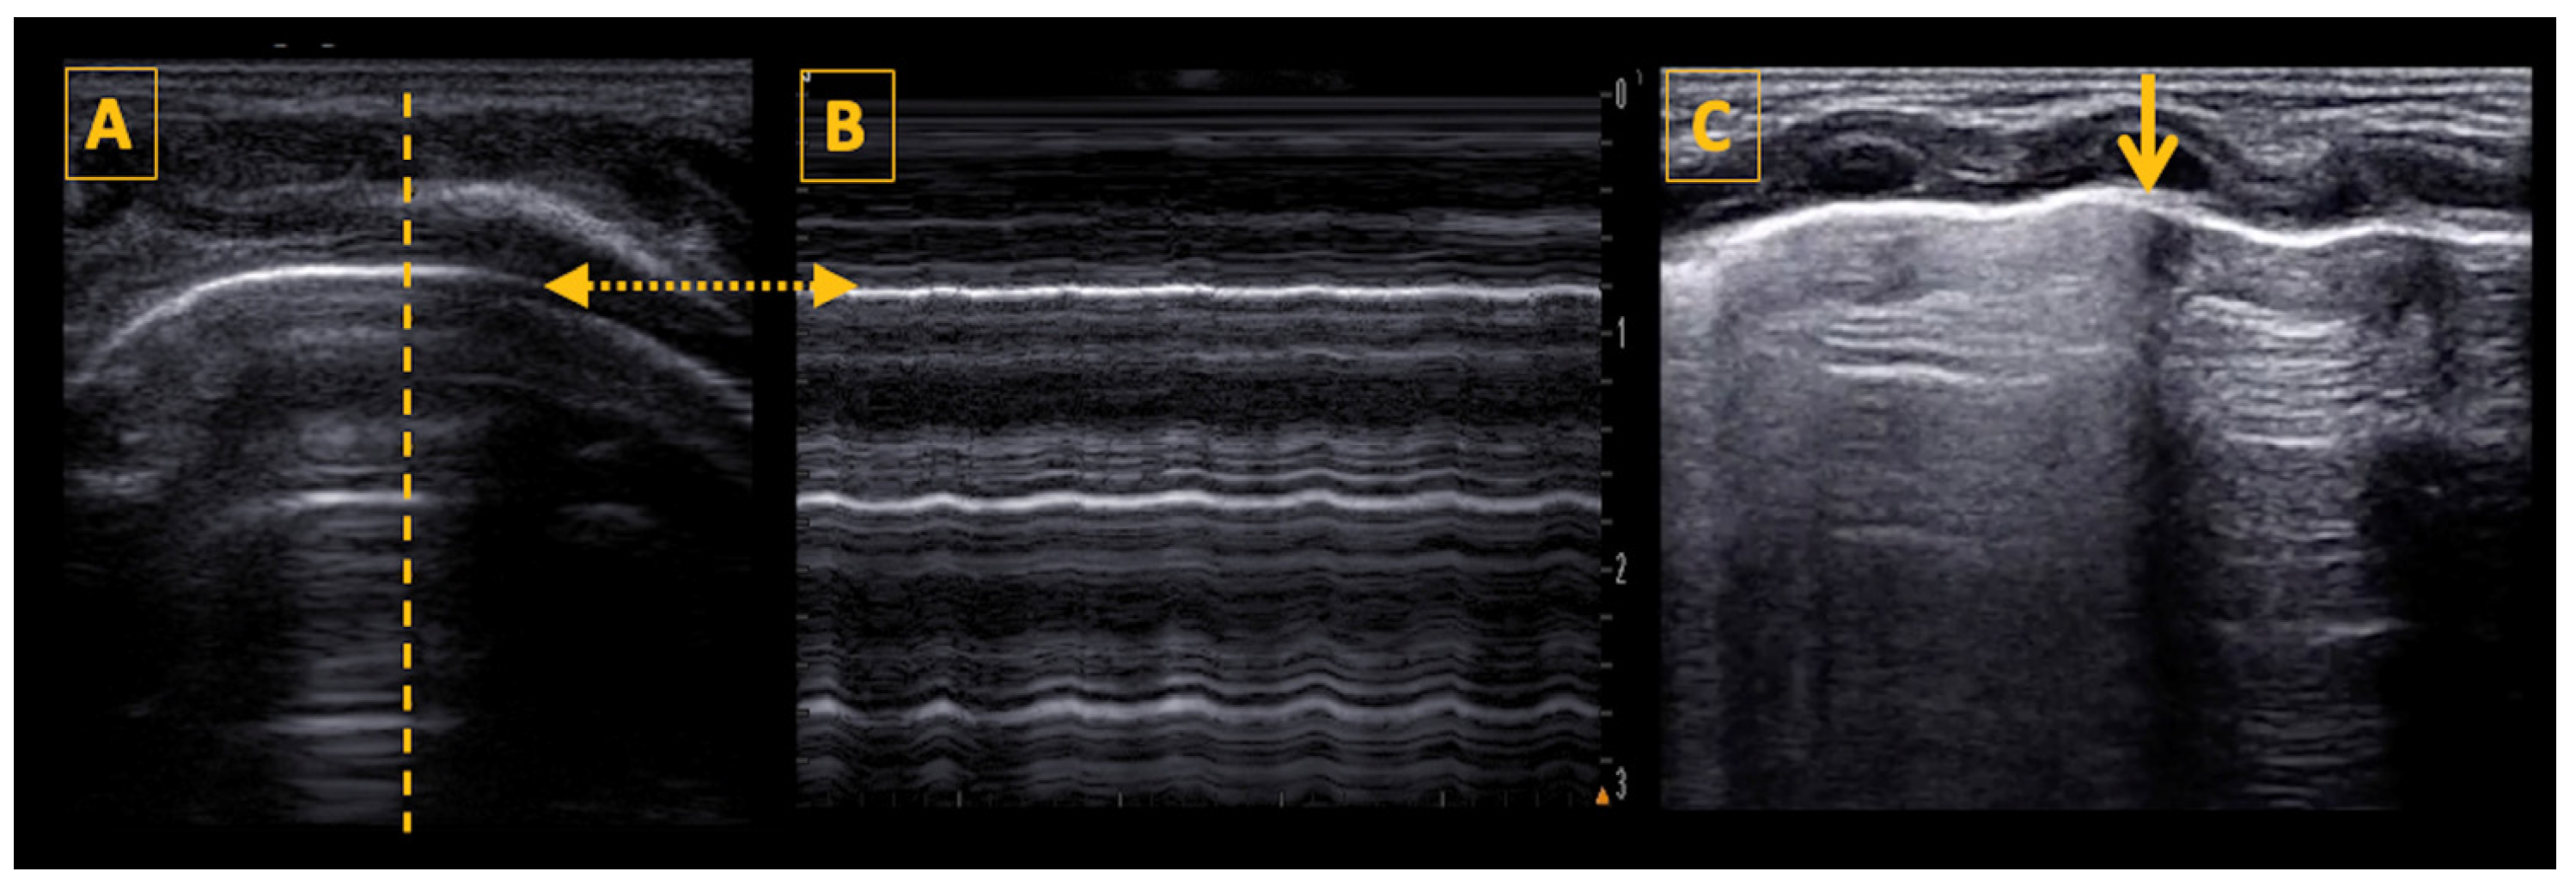

5.2. The Bat Sign

5.3. The Pleural Line, Lung Sliding, and the Lung Pulse

5.4. Lung Ultrasound Features and Signs